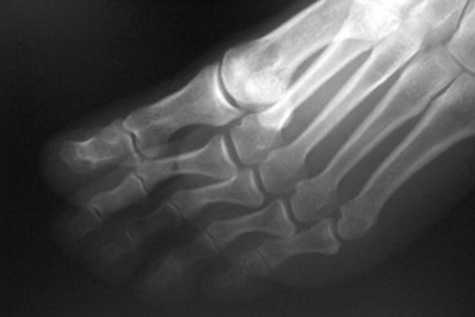

- Болезнь КеллераII. На снимках выявляются патологические изменения в головке пораженной плюсневой кости. В зависимости от срока заболевания может обнаруживаться остеопороз, уплотнение и деформация головки плюсневой кости, ее патологический перелом и дефрагментация.

Формализованный протокол. СТОПА (схема). Болезнь Келера 2.

Определяется деформация и уплощение головки 2, 3, 4 плюсневой кости. На фоне разряжения структуры костной ткани головки дифференцируются плотные островки с четкими, неровными контурами. Дистальный метафиз 2 плюсневой кости несколько утолщен, по всей видимости, за счет периостальных наслоений. Суставная щель во 2 плюсне - фаланговом суставе расширена.

Суставные поверхности, образующие плюсне-фаланговый сустав, инконгруэнтны, форма суставных поверхностей деформирована, уплощена, склерозирована в области . Величина суставных поверхностей увеличена за счет краевых костных разрастаний. Контуры замыкательных пластинок эпифизов ровные, чёткие. Подхрящевой (субхондральный) остеосклероз, как свидетельство функциональной несостоятельности суставных хрящей и свидетельствующий о перегрузке костной ткани, определяется в области . По краям суставных поверхностей определяются костные разрастания (свидетельствуют о функциональной несостоятельности суставных хрящей).

ДИАГНОСТИЧЕСКОЕ ЗАКЛЮЧЕНИЕ:

Остеохондропатия головки 2 плюсневой кости - болезнь Келера 2 правой стопы, картина деформирующего артроза 2 плюсне-фалангового сустава 2 (второй) стадии по классификации Н.С. Косинской.